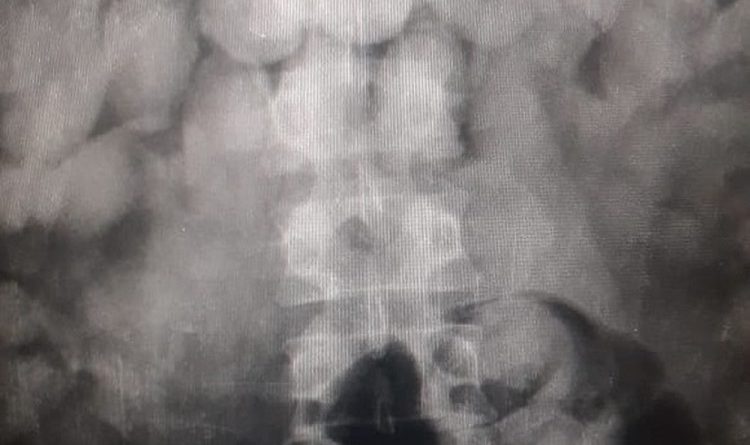

Exames apontam drogas dentro de corpo de suspeitos de tráfico internacional de drogas em Belém. — Foto: Reprodução / Assessoria Polícia Federal

O grupo foi levado para um hospital público de Belém para realizar análises. Os resultados apontaram que eles engoliram de 50 a 100 cápsulas, cada um. Os médicos aguardam os entorpecentes serem expelidos pelos presos.